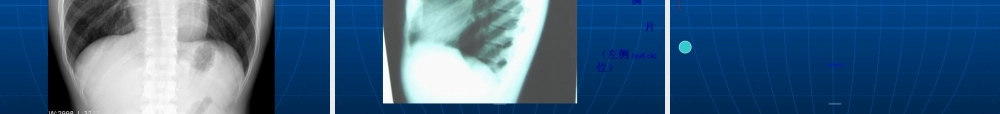

当X线穿过胸部时,由于两肺与其周围的胸壁、纵隔及横膈对X线吸收的差别,产生天然(tiānrán)对比影像,因此呼吸系统疾病应用X线检查较其他系统普遍。近年来,由于CT、MRI、DSA的临床应用,突破了普通X线诊断的限度。但普通X线检查在胸部疾病诊断中仍占主导地位。第第第第第第第第第第1.常规X线检查(jiǎnchá):(1)透视:首选(2)摄片:a.胸部正位片:后前位、前后位;立位、卧位b.胸部侧位片:左侧位、右侧位c.胸部斜位片:左前斜、右前斜d.前弓位片:显示肺尖及锁骨肋骨后方重叠的病变,中叶或舌叶不张,叶间胸膜积液。第第第第第第第第第第由于CT及MRI的应用,X线的一些如体层摄影,高千伏摄影,支气管造影检查已逐步淘汰(táotài),仅属于介入放射学范畴的肺动脉造影,支气管造影及经皮肺穿刺仍经常使用。第第第第第第第第第第2.CT检查:胸部CT扫描较普通X线检查的优越性:⑴密度分辨率高;⑵CT断面无影像重叠,病灶显示清晰;⑶适用于普通胸片表现正常,而临床高度怀疑胸、肺部病变。CT扫描一般用平扫,在需要观察病变与肺门、纵隔血管的关系(guānxì)时,及纵隔有无淋巴结转移时需增强扫描。第第第第第第第第第第3.MRI检查:对纵隔心大血管及胸壁病变有着(yǒuzhe)独特的优点,对肺实质病变效果较差。第第第第第第第第第第第第第第第第第第第第(zhèngcháng)正常胸部X线影像(yǐnɡxiànɡ)是胸腔内、外各种组织和器官的影像(yǐnɡxiànɡ)重叠,熟悉各种影像(yǐnɡxiànɡ)的正常及变异,是胸部影像(yǐnɡxiànɡ)诊断的基础。第第第第第第第第第第(xiōngkuò)包括软组织和骨骼,正常两侧对称。一、胸壁软组织:1.胸锁乳头肌及锁骨上皮肤皱褶:(1)胸锁乳头肌起自胸骨柄及锁骨胸骨端,斜向后止于乳突,在两肺尖内侧形成外缘锐利(ruìlì)、均匀致密的图像。(2)锁骨上皮肤皱褶系锁骨上皮肤及皮下组织的投照。表现为与锁骨上缘平行的3~5mm宽的薄层软组织影,其内侧与锁骨乳头肌影相连。略成直角。当肥胖者锁骨上窝不凹陷,或有肿块时不显影。第第第第第第第第第第第第第第第第第第第第2.胸大肌:于两侧肺野中外带可形成扇形致密影,下缘锐利,呈一斜线与腋前皮肤皱褶连续。一般右侧较明显,不可误认为病变。3.女性(nǚxìng)乳房及乳头:女性乳房可在两肺下野形成下缘清楚、上缘不清且密度逐渐变淡的半圆形致密影,其下缘向外与腋部皮肤连续,勿误认为肺炎。乳头在两肺下野相当与第5前肋间处,有时可形成小圆形致密影...